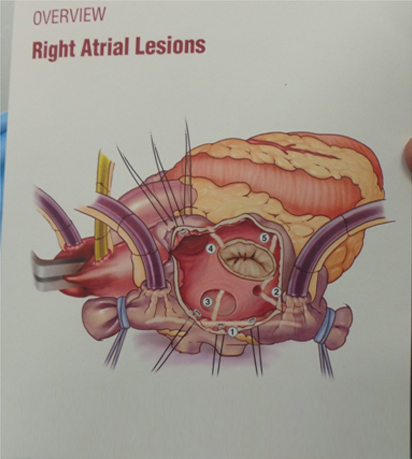

Cardioblate System

Cardioblate System